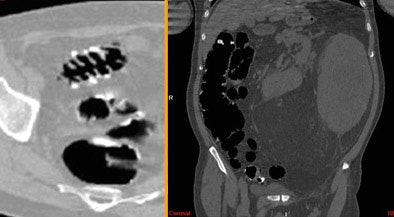

The main causes of incomplete conventional colonoscopy were redundant colon (57%), diverticular disease (40%), and occlusive mass (3%). A large peritoneal liposarcoma was found in one patient whose optical colonoscopy exam had been incomplete.

![]() |

| Above and below: Despite suboptimal distension, VC detected two significant polypoid lesions in the sigmoid colon of a 61-year-old paraplegic with fecal occult blood, following unsuccessful colonoscopy. The patient's parents had both died of colon cancer. Digital subtraction was used to detect the fluid-submerged polyps. |

| In a 72-year-old screening patient with severe diverticular disease, the colonoscope had stopped at the sigmoid colon. VC results showed the colon to be free of disease, but detected a very large extracolonic mass, diagnosed as a peritoneal liposarcoma. |